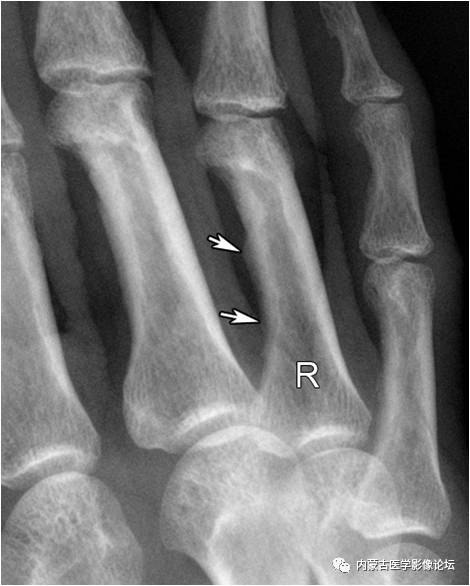

指骨Mach效应:箭头所示为环指(R)与小指骨结构内的软组织重叠影所形成的Mach效应,其走行与滋养血管影相反,也不应误为骨折线。